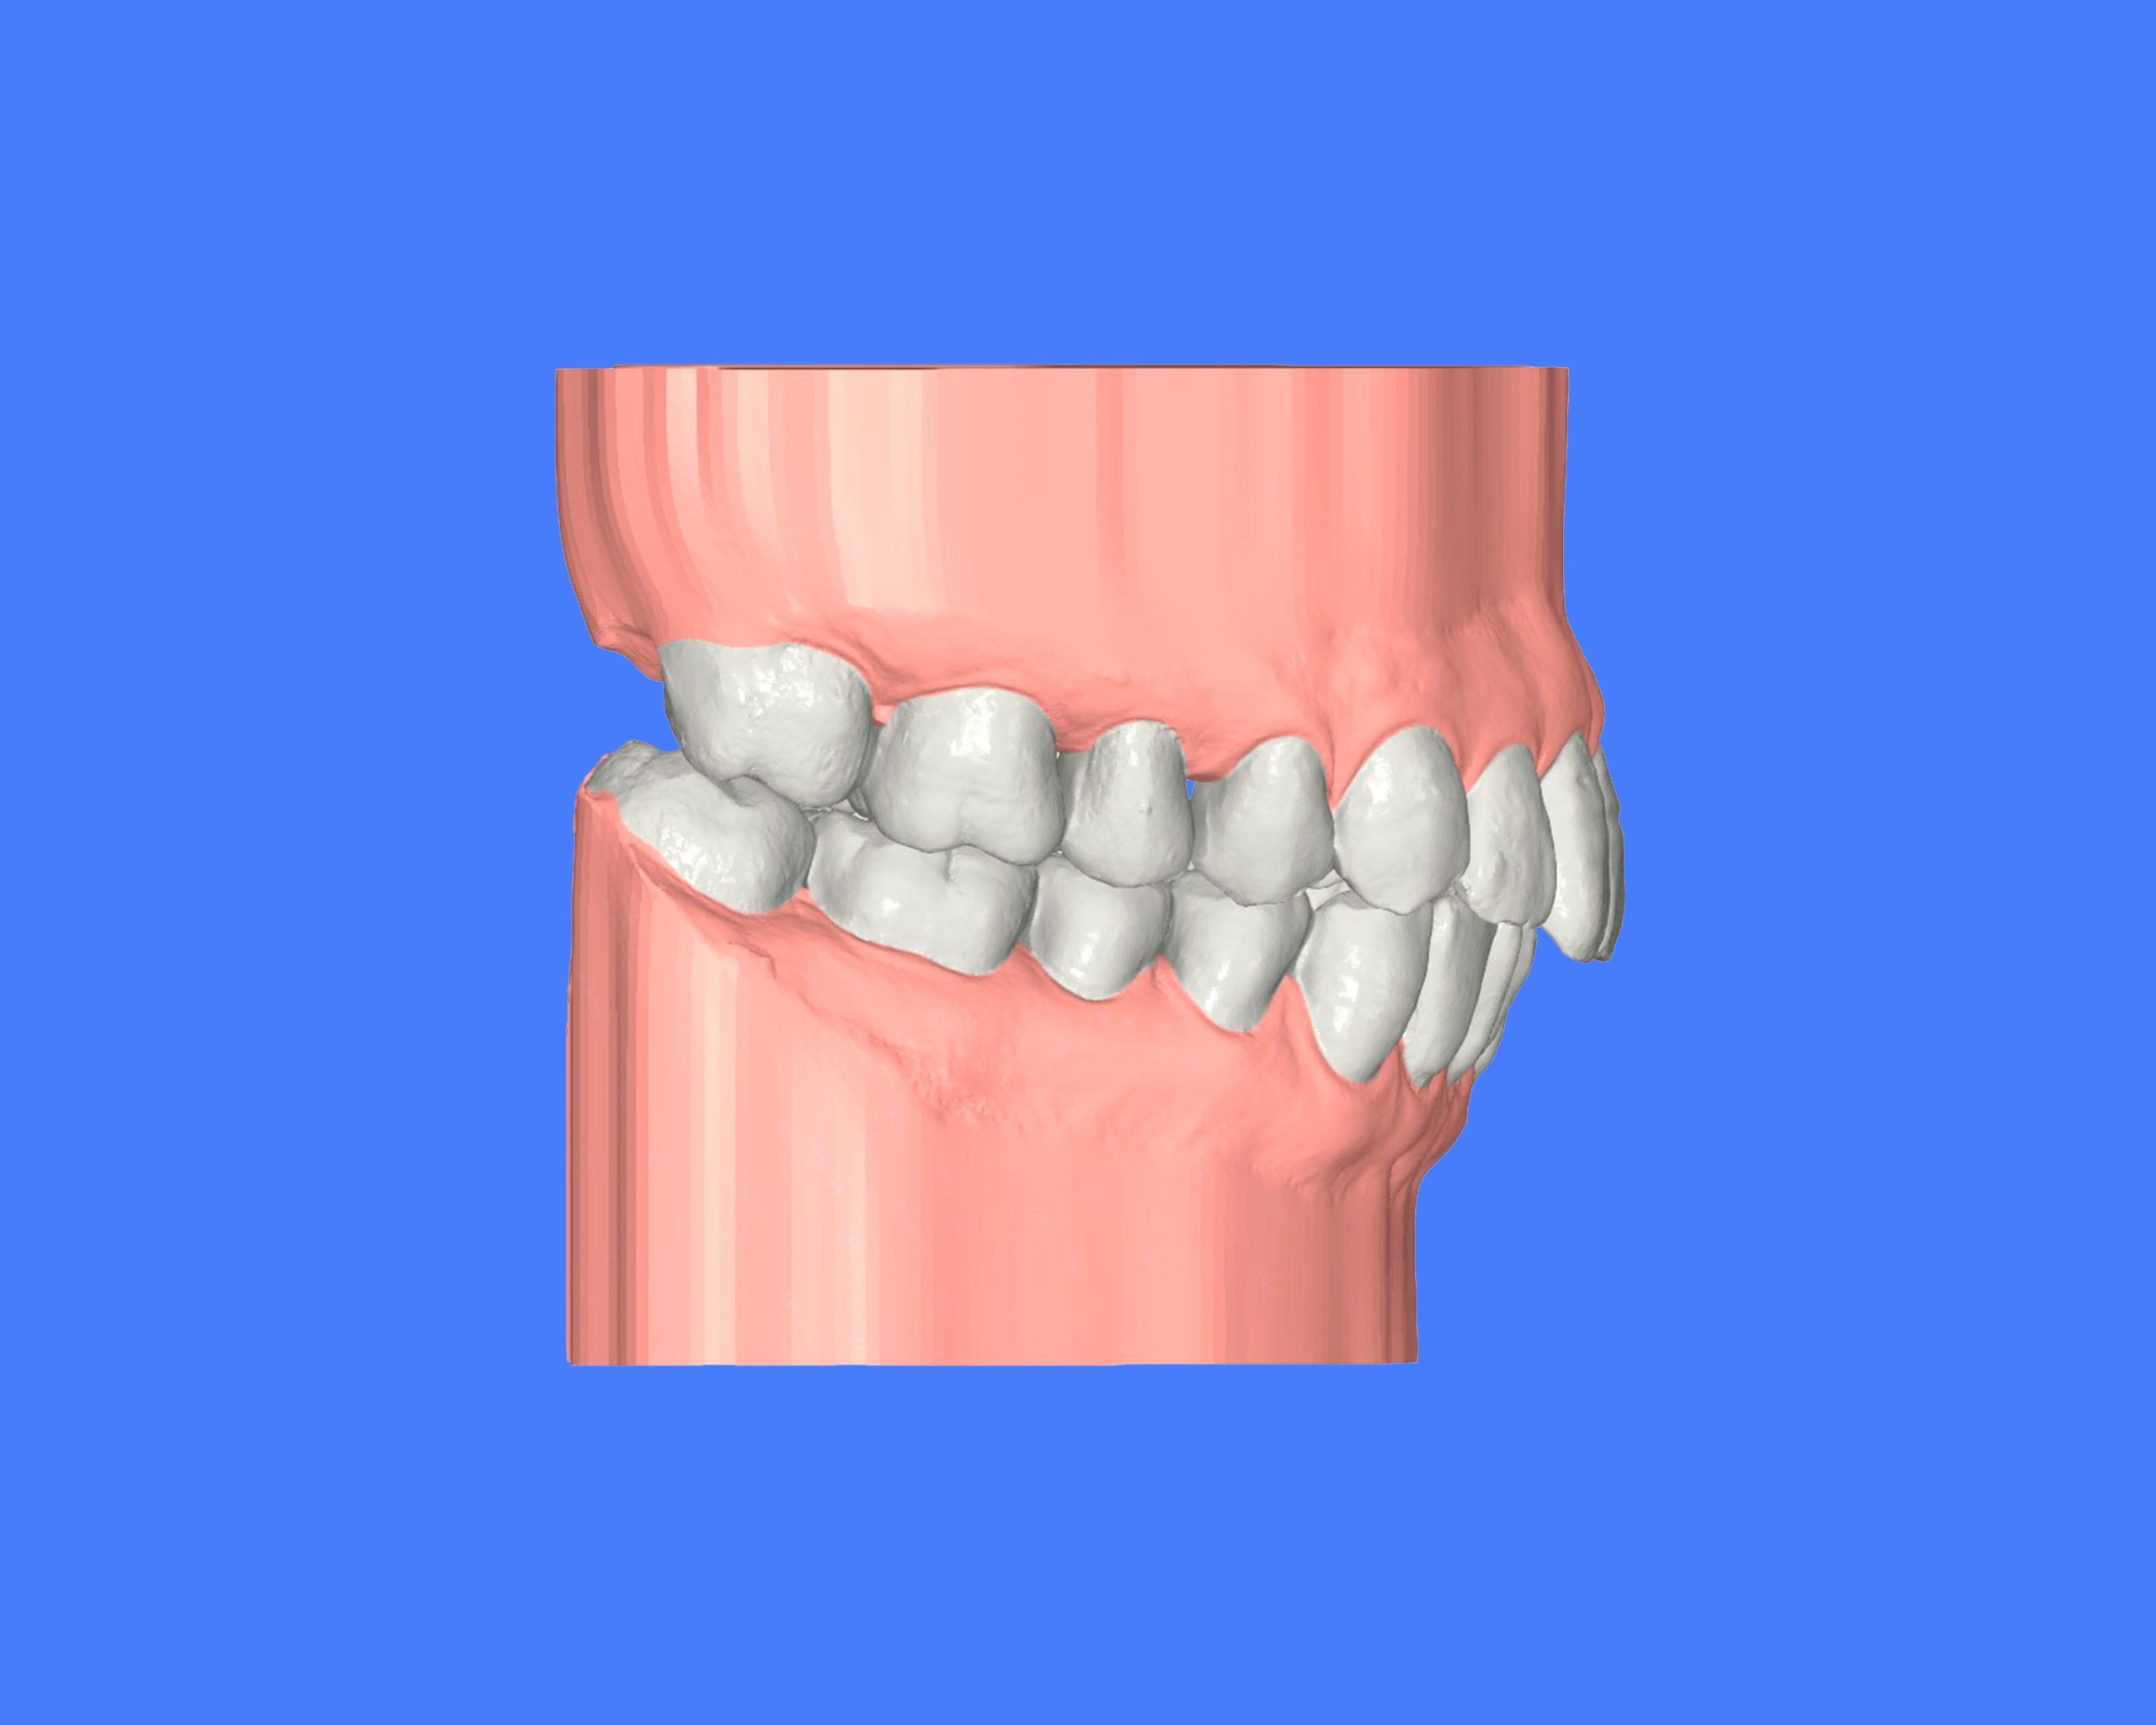

Maloclusión clase II

Se caracteriza por una relación anormal entre los dientes superiores e inferiores, donde los dientes superiores están demasiado adelantados en comparación con los inferiores.

Esto puede generar problemas funcionales, como dificultad para masticar, y también afectar la estética facial.